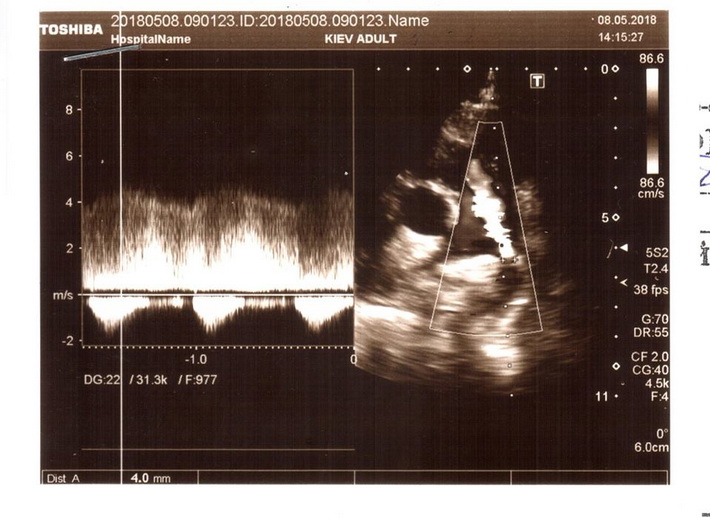

Останнім часом дитина почала швидко втомлюватись, скаржитись на погане самопочуття. Нещодавно при обстеженні було виявлено, що вона має дві вроджені вади серця, про які батьки раніше навіть не здогадувались: відкрита артеріальна протока та двостулковий аортальний клапан.

“Нещодавно ми були на консультації в двох київських кардіологічних центрах – в Науково-практичному медичному центрі дитячої кардіології та кардіохірургії та в Національному інституті серцево-судинної хірургії ім. М.М. Амосова. Кардіохірурги рекомендують якнайшвидше провести операцію із закриття артеріальної протоки. Вартість самого окклюдера складає близько 80 000 грн (без врахування інших витрат). Коштів на придбання окклюдера, а в подальшому – штучного аортального клапана для проведення операцій ми не маємо. Дуже сподіваємось на допомогу небайдужих людей. Будь ласка, врятуйте сердечко нашої донечки!”, – звертається до всіх небайдужих Анна.